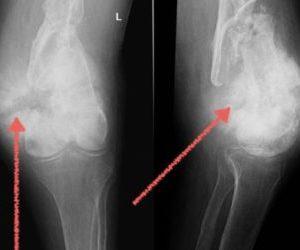

Это разрушение хрящевой ткани в коленном суставе и образование остеофитов, то есть костных наростов. Артроз приводит к деформации, сужению суставной щели и образованию анкилоза. Постепенно, если не проводить лечение, щель между суставами полностью исчезает, и подвижность сустава теряется.

Артроз может развиваться у людей любого возраста. На начальном этапе заболевание протекает незаметно, и боль ощущается лишь после значительных физических нагрузок, после чего она проходит самостоятельно.

На второй стадии болевые ощущения становятся постоянными, и человеку требуется принимать обезболивающие и противовоспалительные препараты. Из-за боли амплитуда движений в колене значительно уменьшается.

На последней стадии происходит полное разрушение хрящевой ткани. Пациент страдает от постоянных болей и теряет возможность нормально передвигаться, в данной ситуации единственным решением может стать операция.